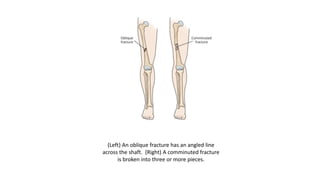

• Oblique fracture: This type of fracture has an angled line across the shaft.

(Left) An oblique fracture has an angled line

across the shaft. (Right) A comminuted fracture

is broken into three or more pieces.